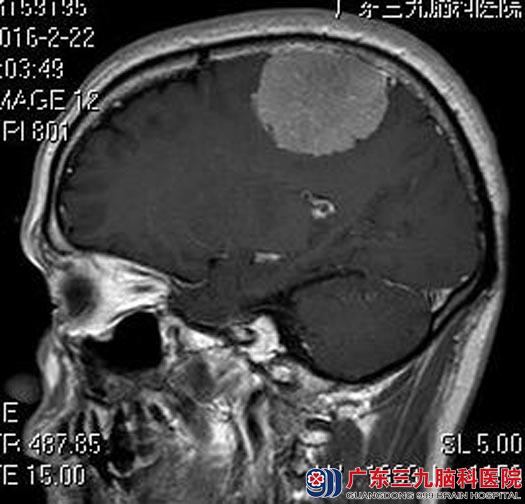

在广东三九脑科医院进一步头颅MR检查显示:顶部镰旁右侧占位,病灶范围约5.5cm×4.5cm×4.2cm,增强后呈较均匀明显强化,邻近脑组织轻度受压。